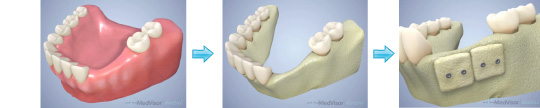

骨造成(自家骨移植、GBR)の流れ

骨が薄くインプラントが植立できないケースでは、自家骨や移植材と膜を併用して骨をつくります。

約6ヵ月待って、十分な骨ができてから、インプラントの植立を行います。